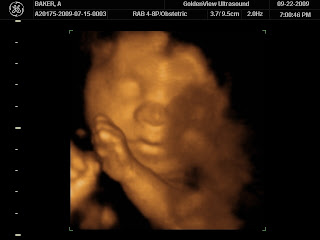

Our 3D/4D ultrasound was amazing yesterday! I am so madly in love with this little angel! I cannot wait for him to get here in December. I think he has Bob's mouth, my chin but I can't figure out whose nose it is. I really can't explain how much my heart bursts everytime I look at these pictures and could have never imagined loving someone I haven't even met this much!

Most everyone that has seen the 3D pictures of Adam all think that he looks like me (or at least my side of the family)! I really can't tell though - all I know is that I don't care who he looks like I am so madly in love with him. I printed out one of the pictures and have it hanging in my cubicle at work and I have to admit I spend A LOT of time just staring at it throughout the day! (Good thing I am not busy at work at all right now). I can't believe he is inside of me and he is made of both Bob and I - really how can anyone question that children are not the greatest miracle from God!